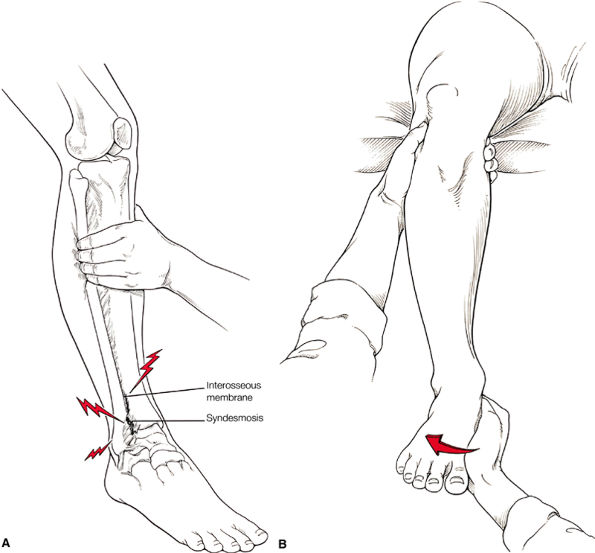

The syndesmotic ligaments consist of the anterior syndesmotic or anterior inferior tibiofibular ligament and the posterior syndesmotic or posterior inferior tibiofibular ligament, the interosseous membrane, and the transverse tibiofibular ligament.

FIGURE 5.59 ● (A) The inferior tibiofibular joint is a fibrous joint. (B) Arthroscopic view of the right ankle demonstrates the syndesmotic ligament and the trifurcation. The trifurcation includes the fibula in the background with the tibia superior and the talus inferior. Approximately 20% of the ligament is intra-articular, and it runs at a 45° angle from the tibia to the fibula.